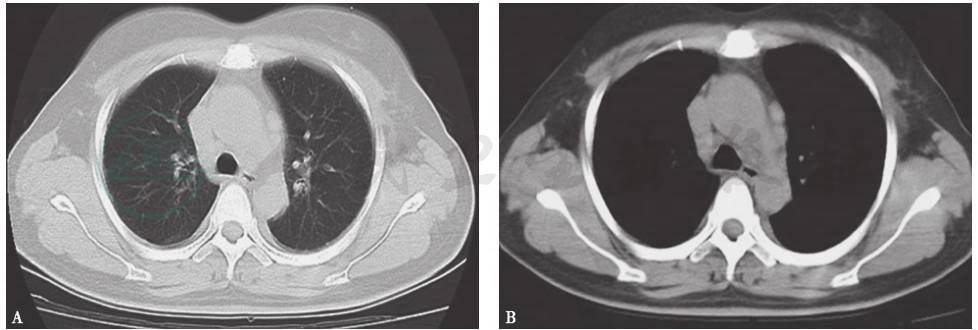

胸部CT:两肺门及纵隔内多个淋巴结肿大,斜裂胸膜区多发小结节,两肺间质纹理增多,双侧胸腔积液,右侧胸腔积液较前明显增多(图8)。

图8 胸部CT表现

引自:呼吸系统疑难病例诊疗辨析.第1版.ISBN:978-7-117-26415-0.主编: